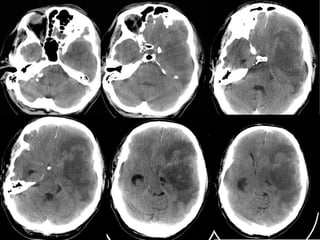

SUBDURAL HEMATOMASUBDURAL HEMATOMA Occursbetween the dura and arachnoid Can cross the sutures but not the dural reflections Due to disruption of the bridging cortical veins Hypodense(hyperacute, chronic), isodense(subacute), hyperdense(acute)

• 12.

Hypodense(hyperacute, chronic),

isodense(subacute), hyperdense(acute)

W=33 L=41